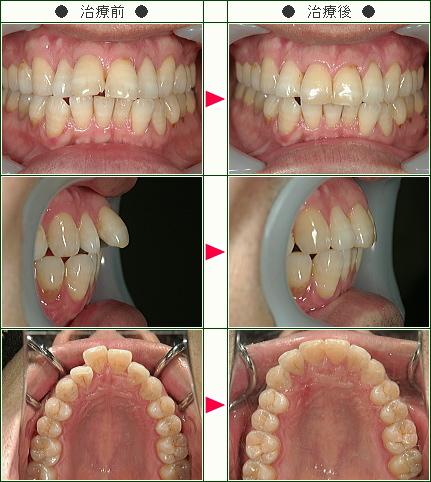

☆出っ歯矯正症例(C・I様 51歳 女性)

☆出っ歯矯正症例(M.M様 47歳 女性)